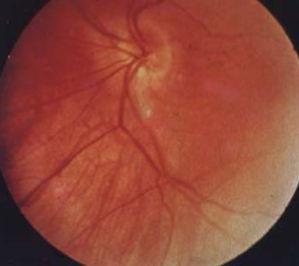

malinserted disc

tilted disc